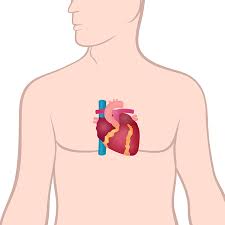

- 심장은 흉강(thorax) 중앙에 위치하며, 흉골(sternum) 바로 뒤, 좌측으로 살짝 치우쳐져 있습니다 :contentReference[oaicite:1]{index=1}.

- 정확히는 흉골 기준 좌측 2/3, 우측 1/3이 차지하며, 양쪽 폐 사이에 있는 중간격(mediastinum)에 포함돼 있습니다 :contentReference[oaicite:2]{index=2}.

- 흉부 2~5늑간(intercostal space) 사이, T5~T8 흉추 레벨로 위치하며, 척추와도 가까운 관계가 있습니다 :contentReference[oaicite:3]{index=3}.